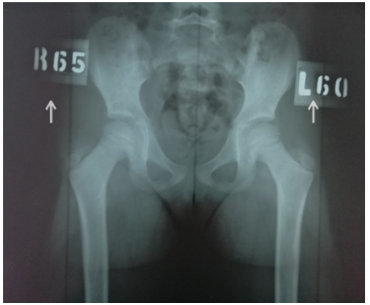

On each radiograph we recommend to mark the angle of femoral internal rotation and right and left sides (Figure 4) to avoid diagnostic and subsequent therapeutic errors.

Figure 4 Radiograph of the hip joints using our original method (the arrows indicate the angle of femoral internal rotation on the right and left, respectively, which corresponds to the clinically defined torsion of the femurs according to Ruwe).